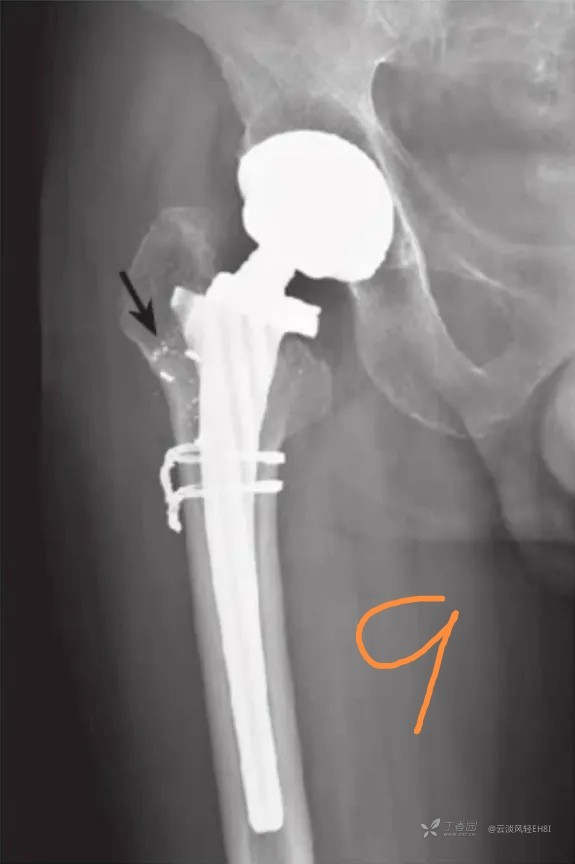

八、假体磨损(图8-9)

常见的有超高分子聚乙烯的磨损,因其透X线,一般是测量相同体位下的假体之间的距离,通过动态观察做出判断;较少见的金属假体磨损,一般的X线片即可显示,通常表现为人工股骨柄周围可见假体磨损碎屑,同时柄部周围骨质吸收溶解,有时需要特殊的体位方能观察到。